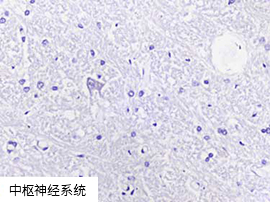

使用 Enzo's AMPIVIEW™ RNA 探针时,SARS-CoV-2 阴性组织无背景染色

|

AMPIVIEW™ SARS-CoV-2 RNA探针 |

AMPIVIEW™ SARS-CoV-2 RNA探针 |

竞品的SARS-CoV-2 RNA探针 |

|

|

|

|

|

"使用其他品牌探针和Enzo AMPIVIEW™ 探针通过ISH检测了一些正常的大脑和胎盘作为SARS-CoV-2 RNA的阴性对照。对比竞品探针的背景(红细胞),使用Enzo探针的背景低。" ——Dr. Nuovo, 俄亥俄州立大学 |